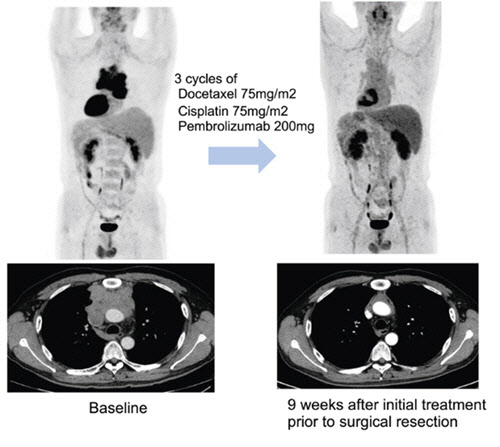

수술에 앞서 3주 간격으로 세 차례 항암화학요법에 면역항암제 펨브롤리주맙을 병용 투여한 결과병리학적으로 완전 관해를 보인 환자 예시. 연구팀은 이 환자가 3기 흉선암이었으나 현재 3년 이상 재발 없이 경과 관찰 중이라고 밝혔다. 연구팀은 “수술 시행한 환자 중 약 18%의 환자에서 완전 관해, 약 46%의 환자에서는 잔여 생존암이 10% 이하인 주요 부분 관해(major pathologic response)가 관찰됐다”고 밝혔다.

연구팀은 추적관찰 기간 27.5개월(중앙값) 동안 전체 환자의 57.5%(23명)에서 수술 전 치료를 통해 종양의 크기가 유의미하게 감소하는 반응을 보였다고 했다. 또한 82.5% 환자에서는 해당 치료로 인해 질병의 진행이 억제 되는 질병 조절이 관찰됐다고 전했다.

수술을 받을 만큼 암이 줄거나 반응을 보인 덕분에 전체 환자의 70%(28명)가 수술을 받았다고 밝혔다. 치료 결과 병리 검사를 통해 암세포가 10% 이하로 감소한 지를 평가(MPR)했을 때 전체 환자의 32.5%(13명)가 도달한 것으로 나타났다. 당초 기대치 50%에는 미치지 못했지만, 수술 환자 놓고 보면 MPR 도달 비율은 46.4%로 증가해 펨브롤리주맙이 흉선상피종양 치료 선택지에 포함될 가능성에 파란불이 켜졌다.